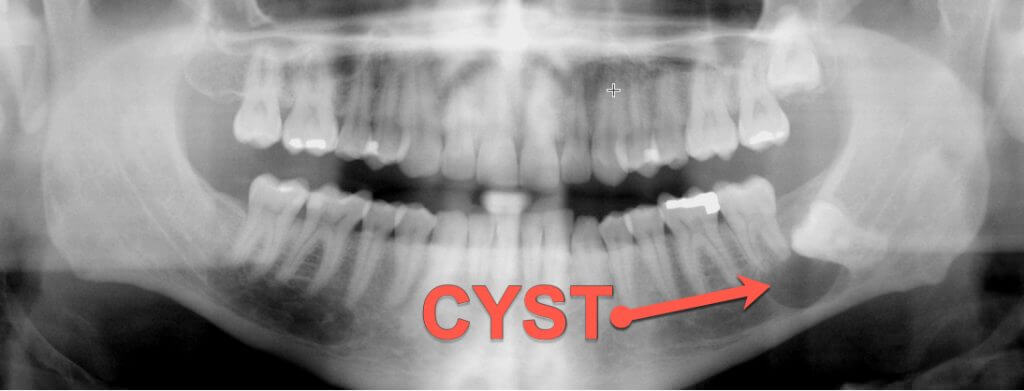

A regular dental x-ray will allow your dentist to diagnose dental disease and track the progress of treatments. They are invaluable tools Dr. Rimes can use to identify problems before they become something more serious. A dental x-ray can do all of the following: Identify tooth decay – decay, especially between the teeth and around […]